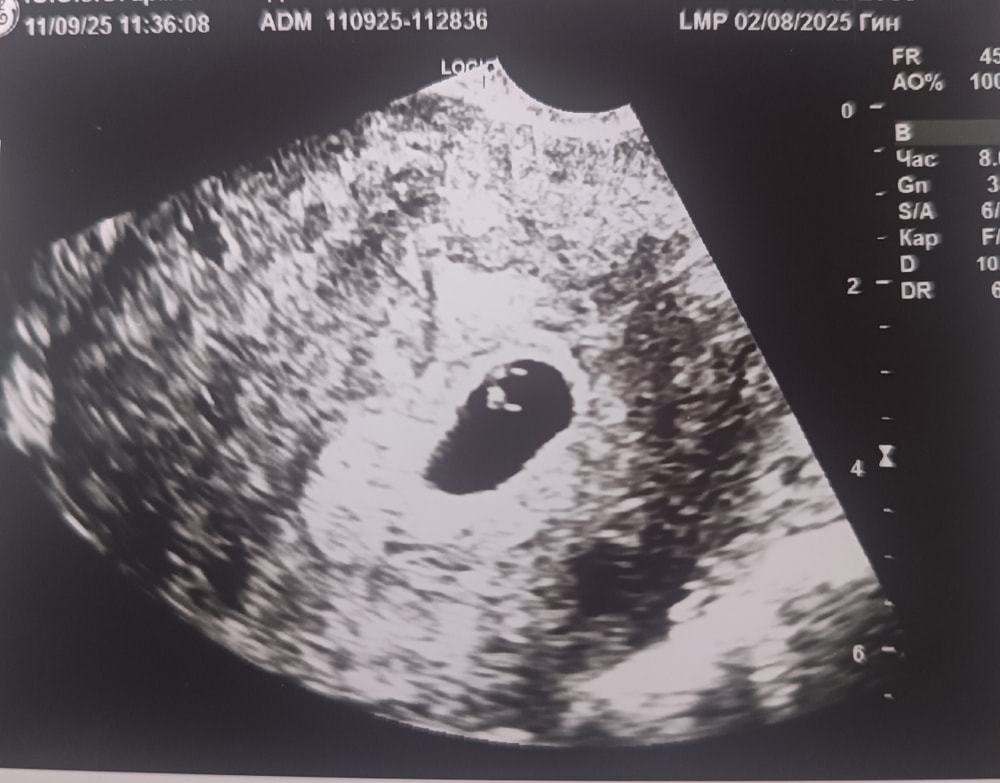

Плохое плодное яйцо